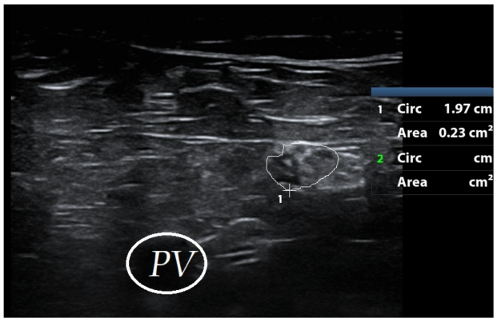

High resolution ultrasonography of the right common peroneal nerve revealed enlarged cross-sectional area (Figure 3 [Fig. 3]).

Figure 3: Increased cross-sectional area of right common peroneal nerve encircled with white line (Landmark: Popliteal vessels [PV], Normal cross sectional area – 6 mm2).